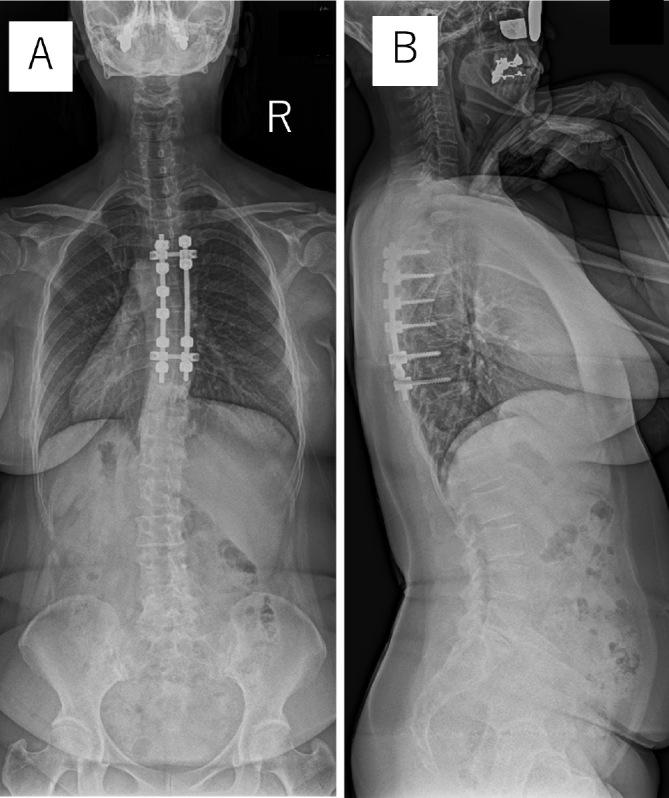

A Case of an Iatrogenic Pseudomeningocele after Thoracic Spinal Cord Tumor Surgery with a Long-Term Follow-Up.

Spine Surg Relat Res. 2024 Mar 11;8(4):466-468. doi: 10.22603/ssrr.2023-0242. eCollection 2024 Jul 27.